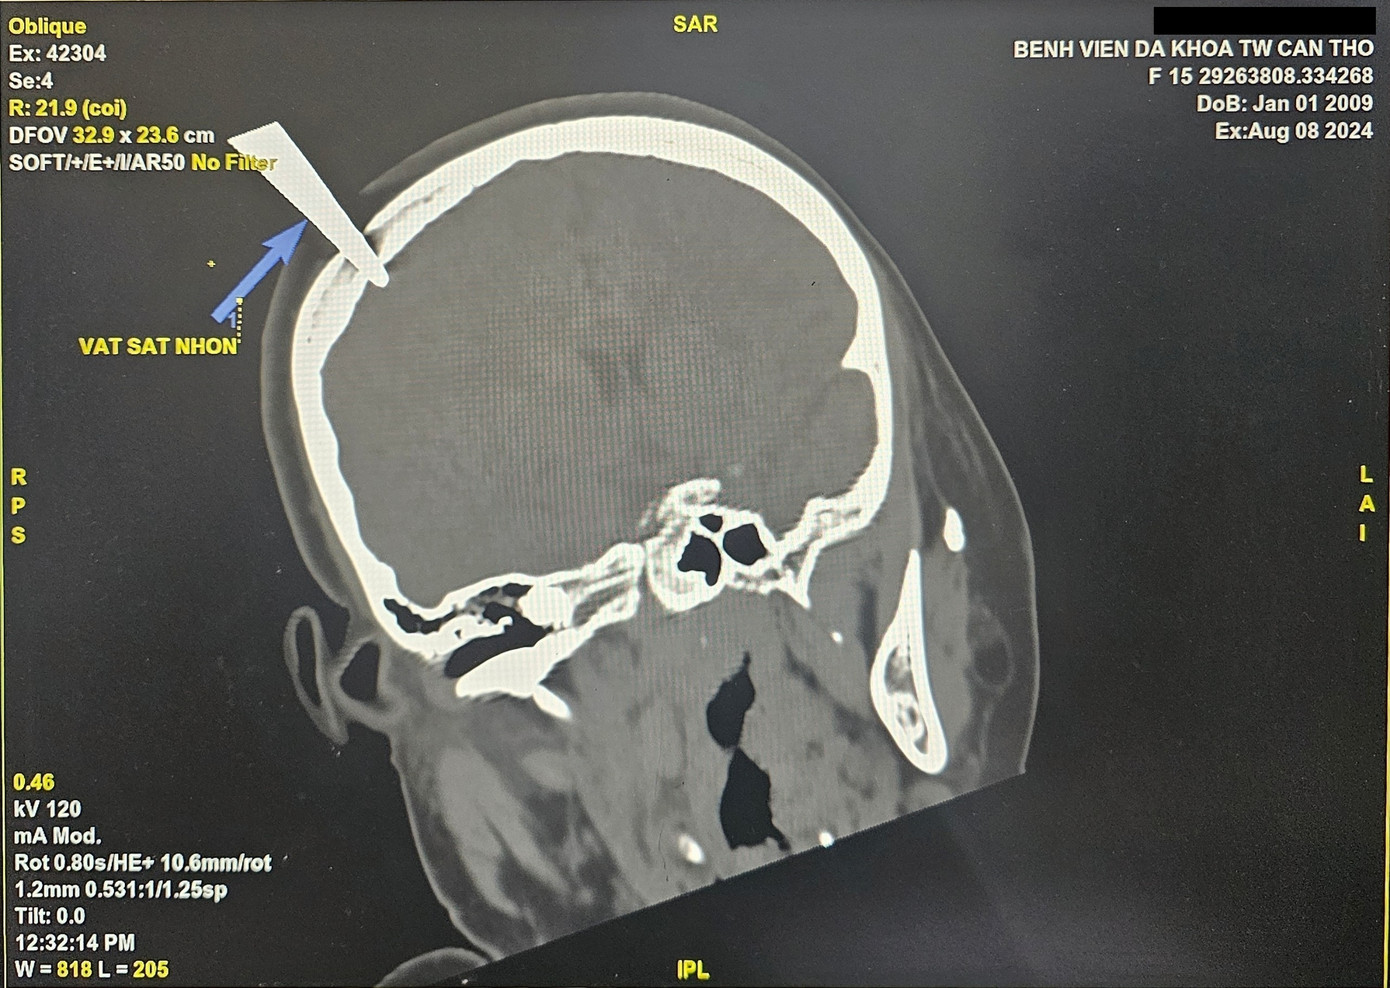

Theo đó, bệnh nhân N.T.C.T. (15 tuổi, ngụ Sóc Trăng) được đưa vào bệnh viện cấp cứu trưa 8/8, với chiếc kéo vẫn cắm xuyên sọ vùng đỉnh đầu phải.

![]() |

| Hình ảnh kéo đâm xuyên qua sọ bệnh nhân. |